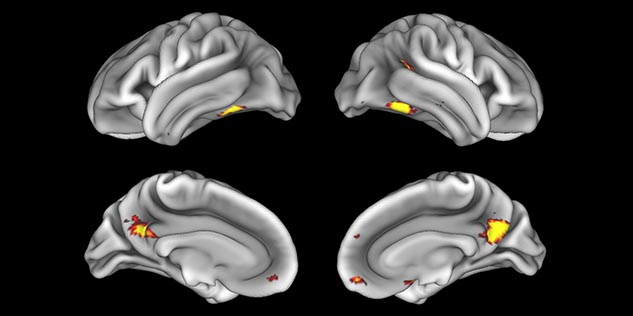

BOLD fMRI activation, depicted in color, of left anterior insula (MNI plane z = 8 mm) in a single subject by a contrast between viewing and matching faces with negative emotion (angry, sad, scared) versus happy faces. The voxelwise threshold is p < 0.001, and colored voxels survive false discovery rate correction to p < 0.05. The activated voxels in color are overlaid on the subject's own 3D-TFE image displayed in grayscale, after transforming the data to MNI space. The fMRI pulse sequence was a single shot FFE echo planar acquisition using MultiBand SENSE factor 6, dS SENSE factor 1, isotropic voxel size 2.4 mm, 60 transverse slices, TR 950 ms, TE 30 ms, flip angle 52 degrees, 517 dynamic scans, total scan duration 8:21 minutes. Image provided by James M. Bjork, PhD, Associate Professor of Psychiatry at VCU.